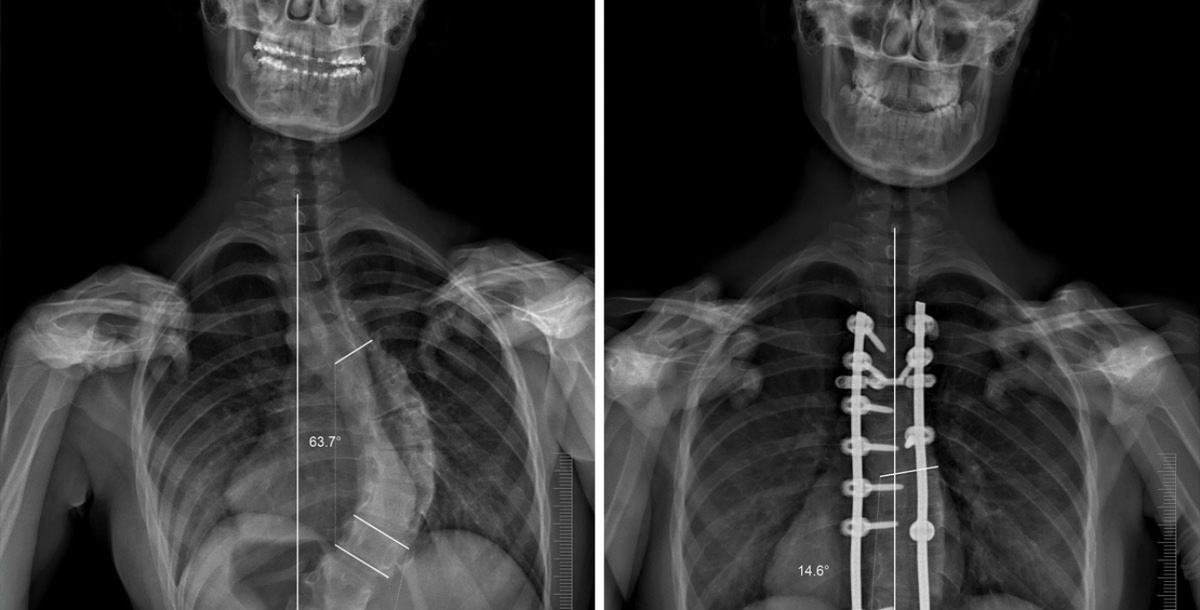

На снимках можно увидеть, как поменялся позвоночник после операции по исправлению искривления

Эффект впечатляющий даже наглядно. Ведь после операции человек буквально сразу вытянулся на целых пять сантиметров вверх.